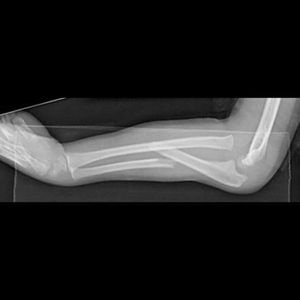

What’s the name of this #and it’s reverse ??!

Monteggia fracture. ..counter one is galezzi fracture

Monteggia fracture

Fracture of ulnar shaft

Fracture of ulna